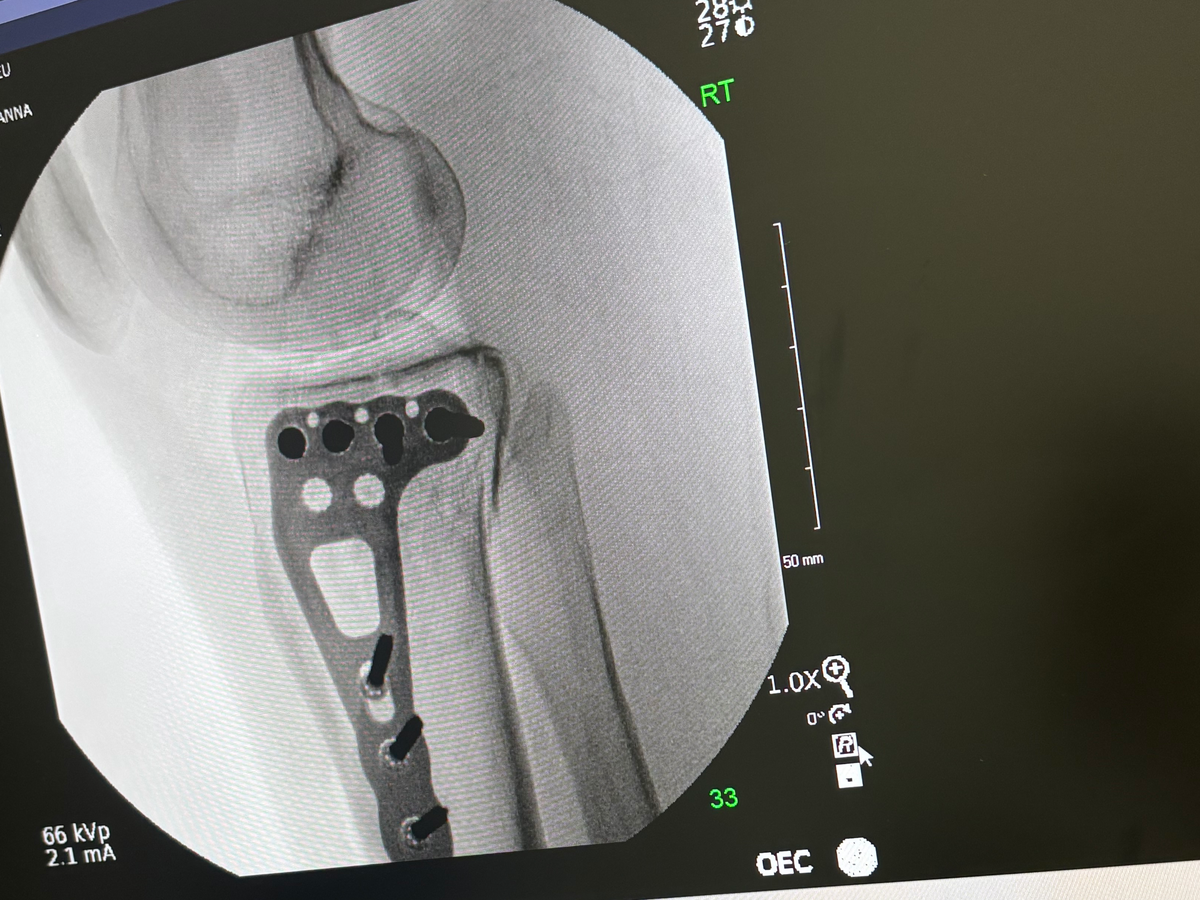

My name is Leanna Checchia. I am reaching out to share my story and seek assistance during an incredibly difficult time. Earlier this month, after enduring years of domestic abuse, I faced what I believe was a final attempt on my life. As a result, I sustained severe injuries and was diagnosed with a tibial plateau fracture, which required emergency surgery. In addition to these physical injuries, I am also coping with Post-Traumatic Stress Disorder (PTSD) stemming from the abuse.